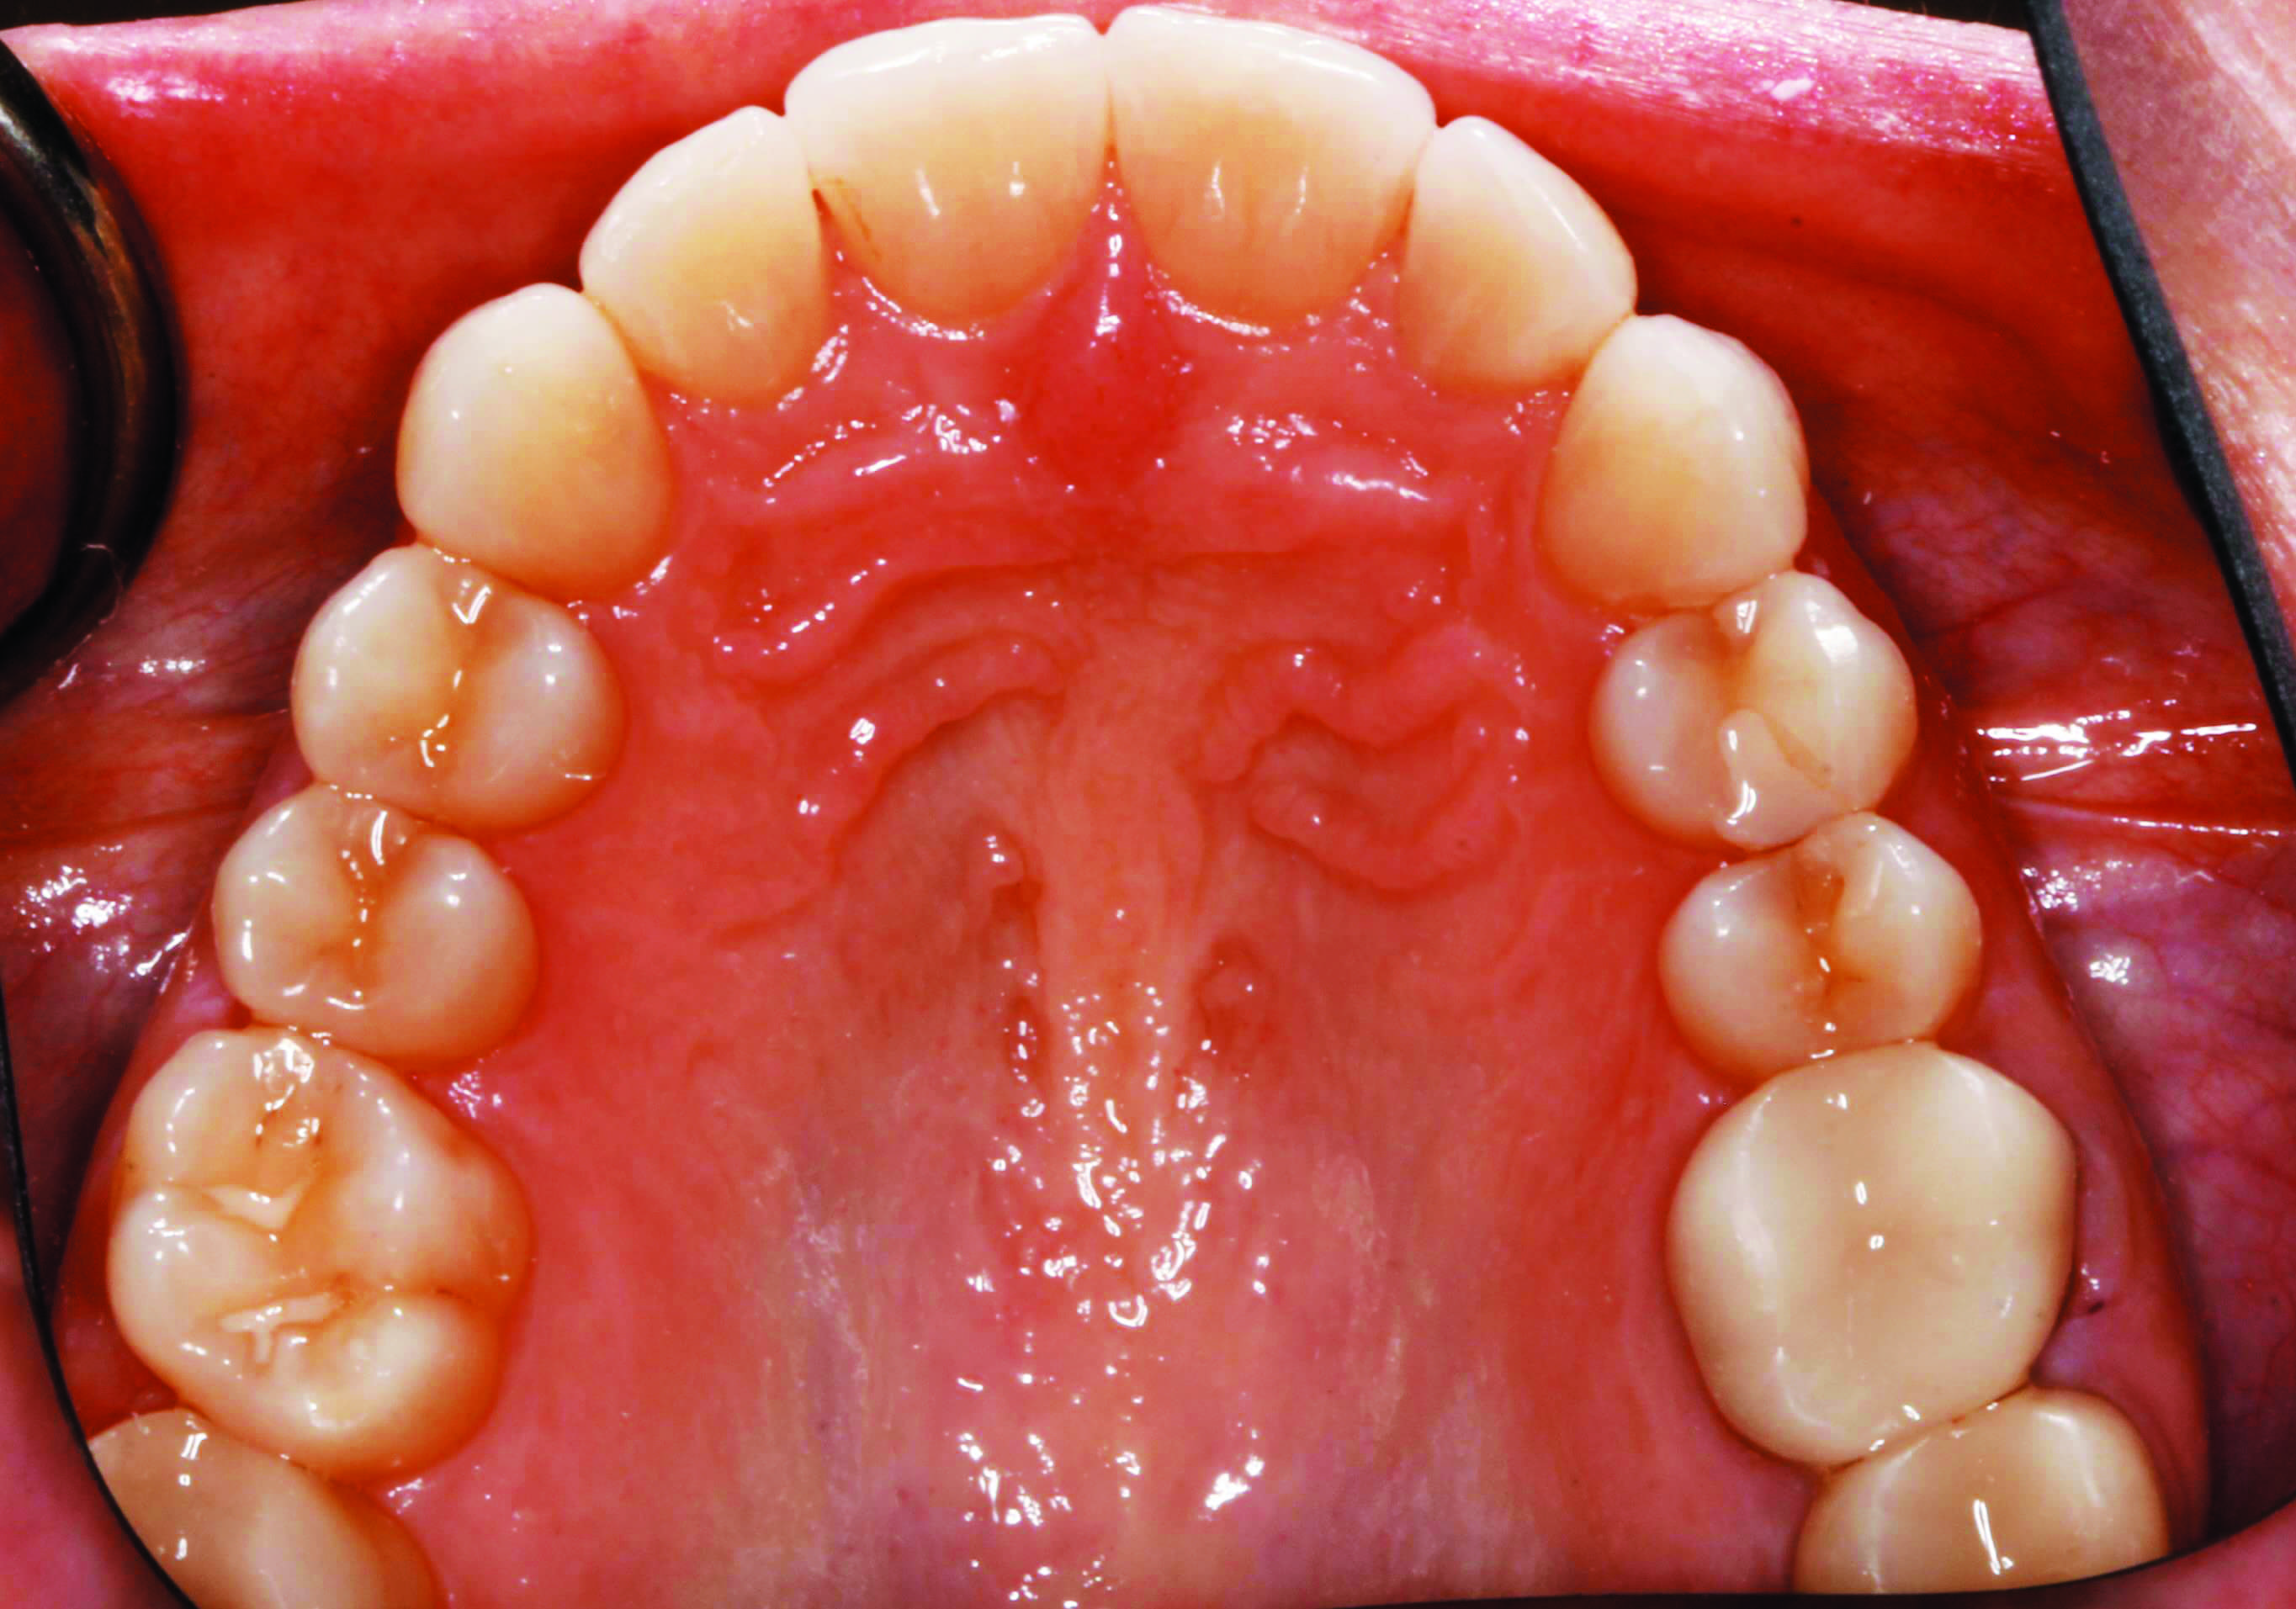

Before and after 14 aligner trays and 13 refinement trays D Aligner Refinement It is not a bad thing if your dentist suggests refinements, it just means that they are making sure you get the most out of your treatment. Each aligner is designed to put the right amount of pressure on your teeth to move and realign them into their ideal positions. Invisalign refinements are corrections to your aligner treatment after you. Aligner Refinement.